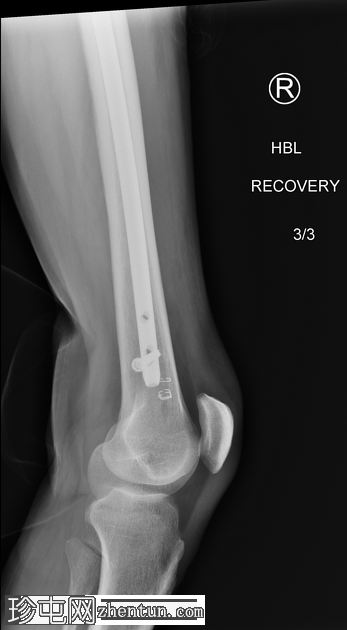

4.jpeg

正面

术中恢复期影像学检查:股骨髓内钉固定穿过小转子水平处已知的溶骨性病变。无金属部件损坏或假体周围骨折。

患者随后接受了股骨近端置换术。

无金属部件损坏。